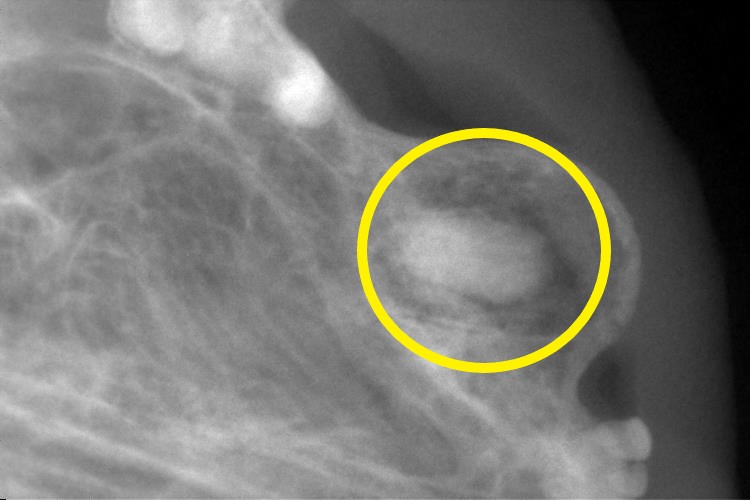

右上顎の犬歯のレントゲンです。

歯根が残っていることが分かります。(〇印)